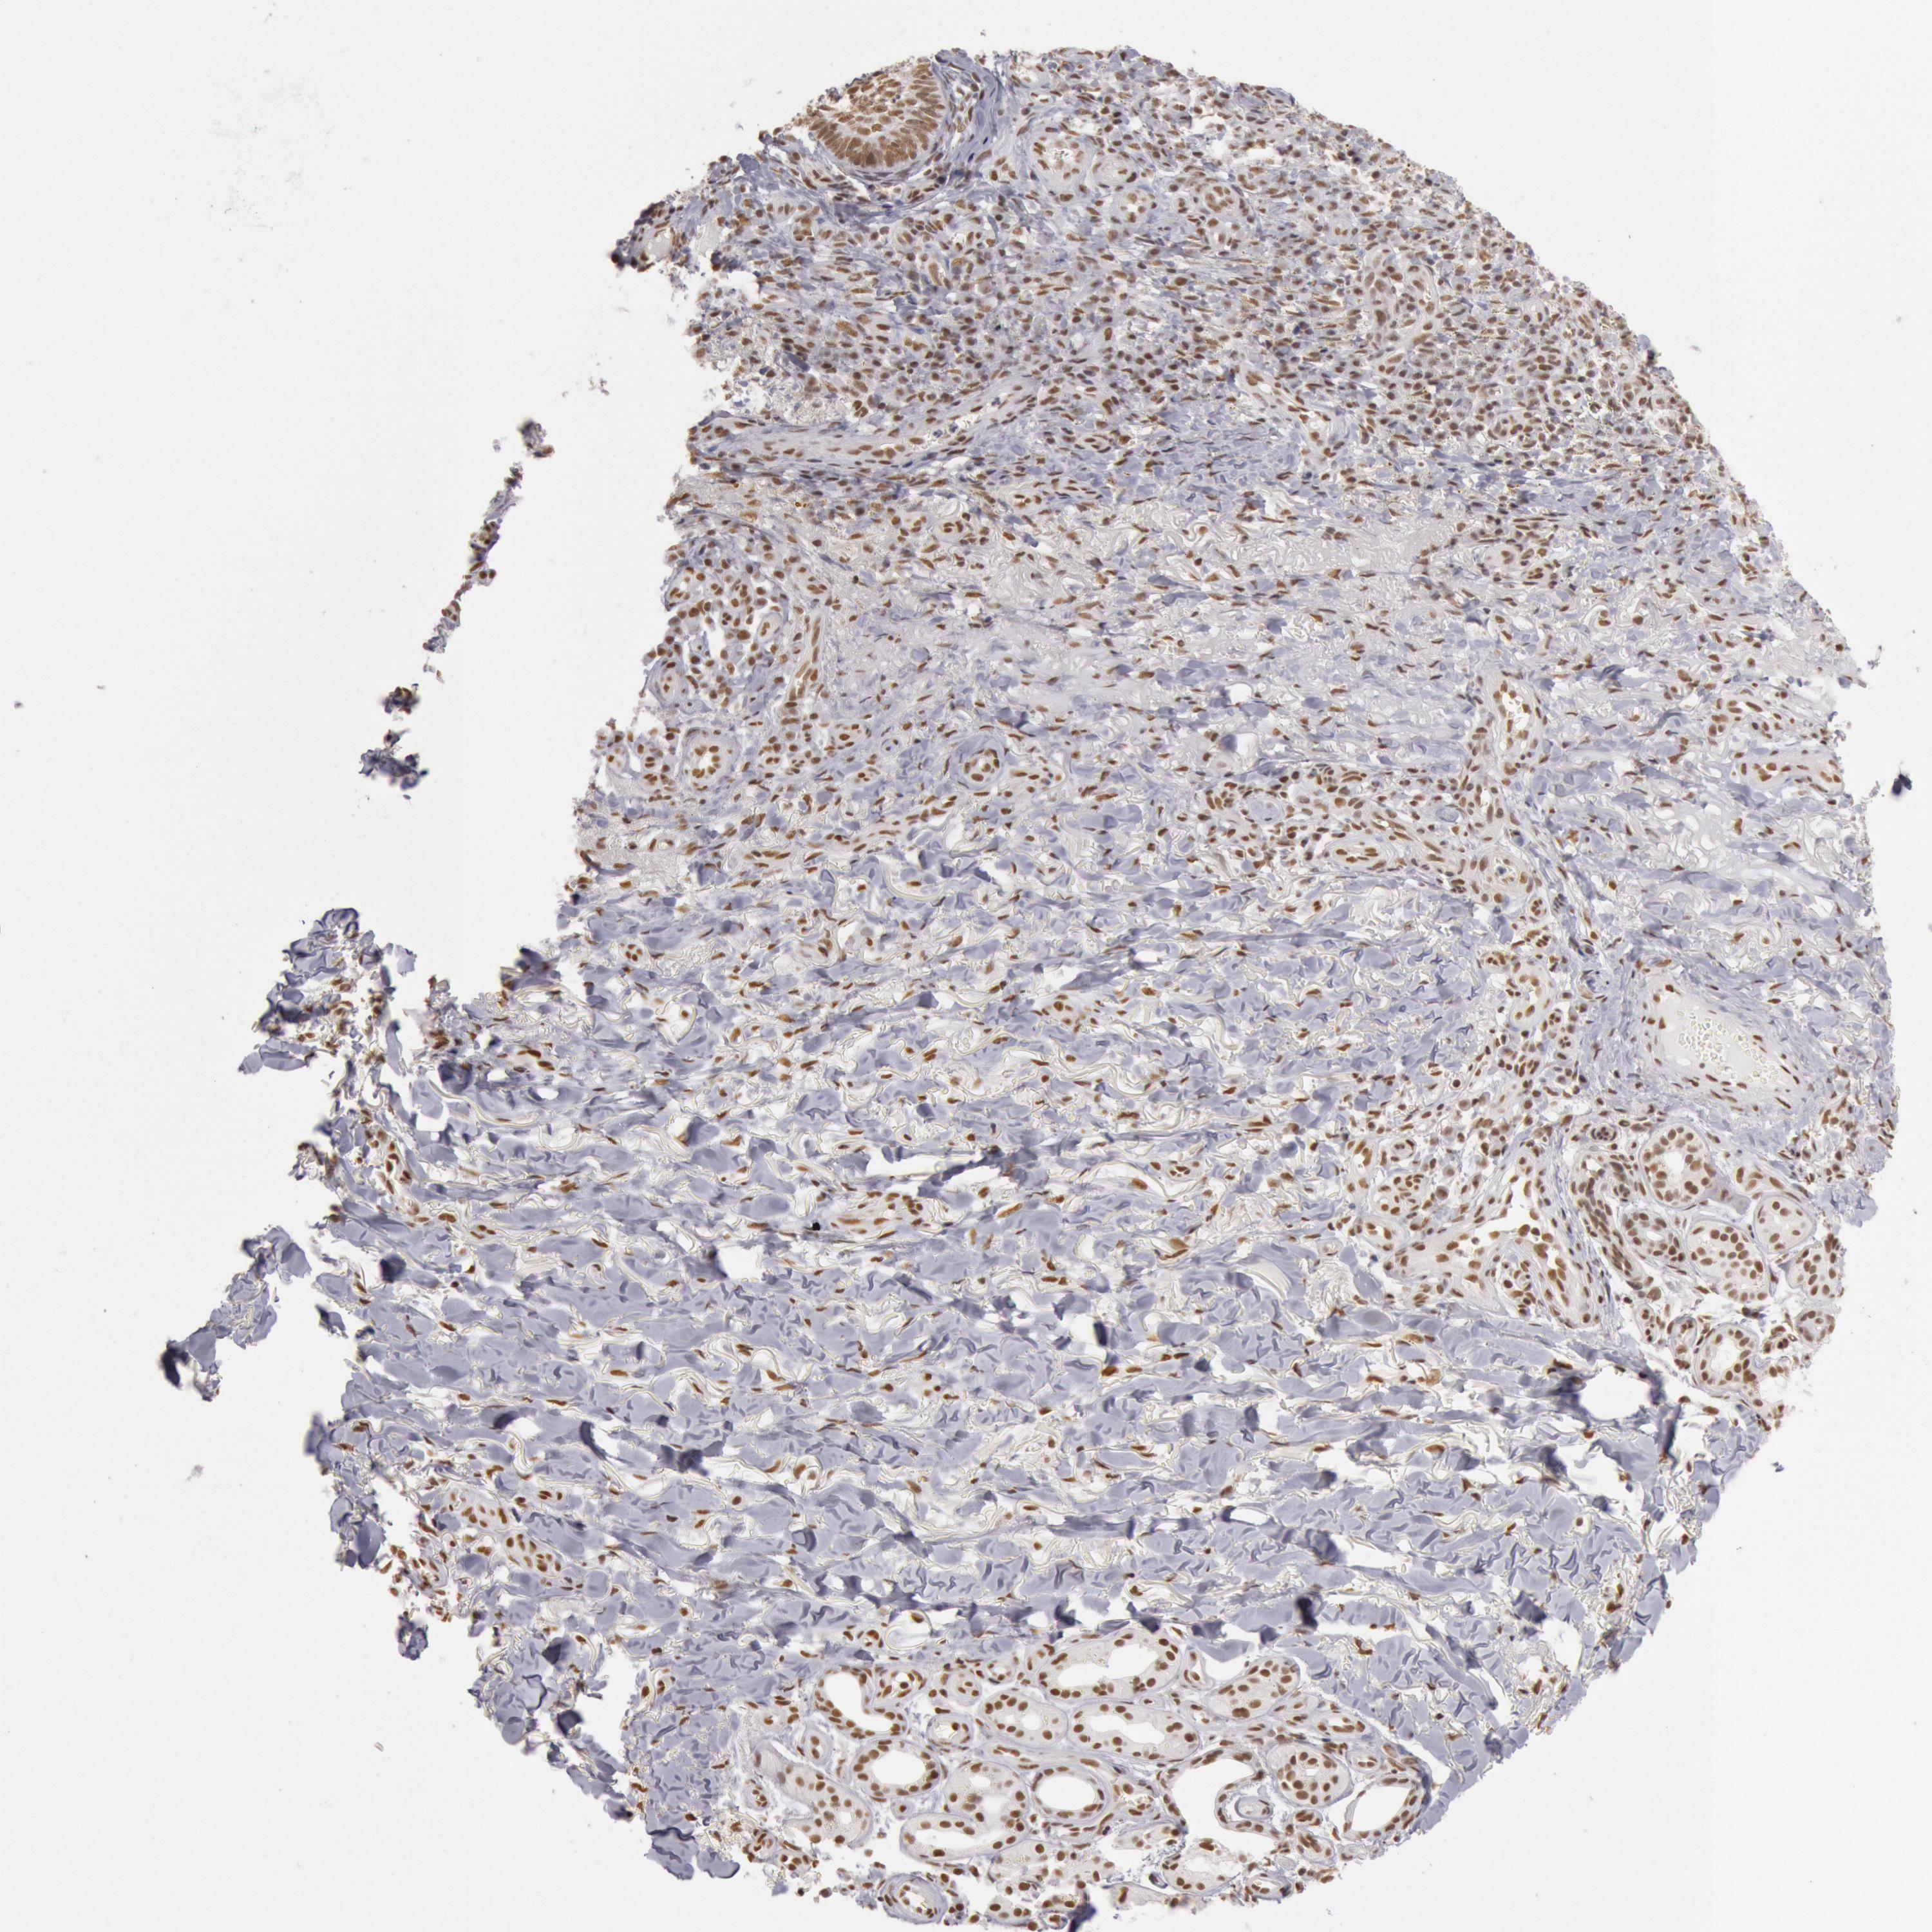

SKIN CANCER - Protein expressioni

A mouse-over function shows sample information and annotation data. Click on an image to view it in a full screen mode. Samples can be filtered based on level of antibody staining by selecting one or several of the following categories: high, medium, low and not detected. The assay and annotation is described here.

Antibody stainingi

Antibody staining in the annotated cell types in the current human tissue is reported as not detected, low, medium, or high, based on conventional immunohistochemistry profiling in selected tissues. This score is based on the combination of the staining intensity and fraction of stained cells.

Each image is clickable and will lead to virtual microscopy that enables deeper exploration of all samples and also displays staining intensity scores, fraction scores and subcellular localization as well as patient and tissue information for each sample.

Antibody HPA001221

Antibody HPA001222

Staining

High

Medium

Low

Not detected

Intensity

Strong

Moderate

Weak

Negative

Quantity

>75%

75%-25%

<25%

None

Location

Nuclear

Cytoplasmic/membranous

Cytoplasmic/membranous,nuclear

Squamous cell carcinoma, NOS

Basal cell carcinoma